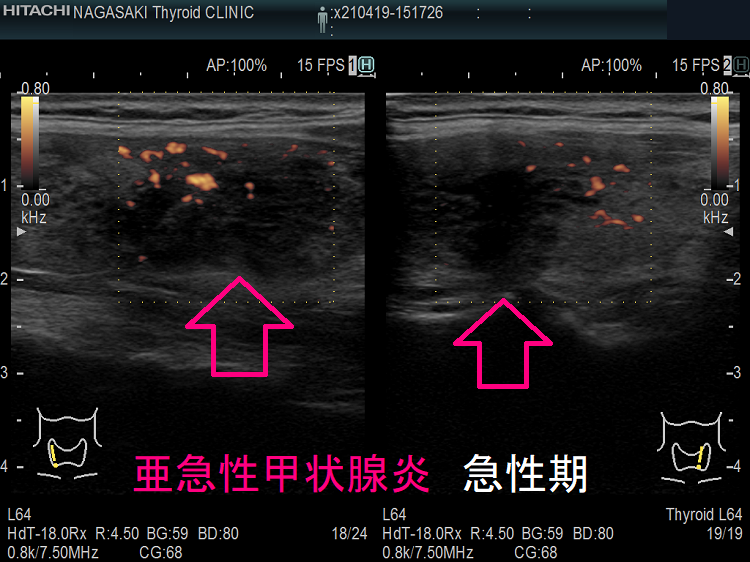

- 甲状腺超音波(エコー)検査で亜急性甲状腺炎に特徴的な所見;痛みがある・あるいはあった炎症の強い部分に一致して、エコー輝度が低く、黒色に見えます。同部は

①急性期には血流が乏しく、ドプラーモードで無血流になります(回復期には血流増加)

②硬く(癌より癌らしい硬さ)、エラストグラフィーで青く見えます。)